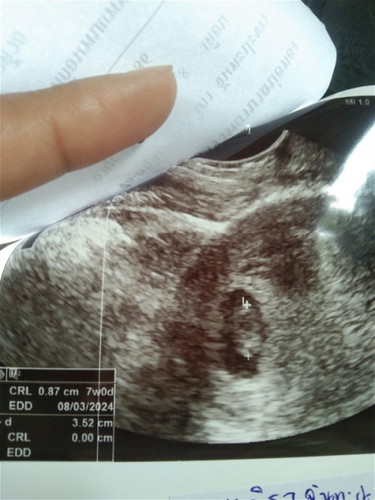

มีกรณีแม่ๆคนไหนท้อง7w อัลตร้าซาวด์เจอเด็ก แต่ไม่ได้ยินเสียงหัวใจเด็กบ้างมั้ยค่ะ

ตอนนี้เราเครียดมาก วันนี้รู้สึกปวดท้องน้อยเกร็งท้องไปหมดเลยไปหาหมอ คุณหมอตรวจพบทารกแต่ไม่ได้ยินเสียงหัวใจเด็ก แถมมีภาวะแท้งคุกคาม หมอบอกจริงๆอายุครรภ์ควร9w4dแต่ตรวจแล้วได้7w เอง เรื่องเสียงหัวใจหมอบอกน้องตัวเล็กหรืออาจจะเสียชีวิตในครรภ์แล้วถึงไม่ได้ยินเสียงหัวใจ ท้องแรกเราหวังมากอยากมีเขา อยากให้เขาเกาะท้องเราแน่นๆ วันจันทร์นี้ไปฝากครรภ์ไม่รู้จะเป็นยังไง😔 # ท้องแรก#แท้งคุกคาม